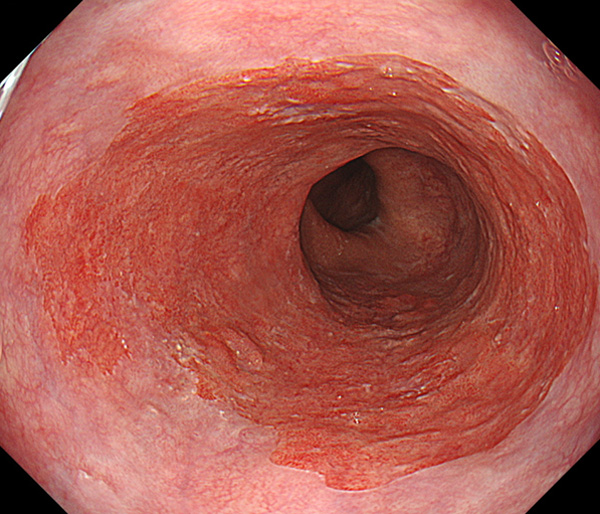

内視鏡所見と病理組織像の1対1対応が可能な症例を公募いたします。主にLSBEに発生した早期癌(HGDを含む)を対象としますが、興味深い症例であればSSBE癌でも結構です。採否は世話人へご一任ください。

特に、本邦では極めて稀なlong segment Barrett’s esophagus(LSBE)から発生した早期癌は、診断に難渋する場合も多く、欧米ではランダム生検による検出が標準的とされています。背景のBarrett食道もろとも全体を内視鏡切除+ラジオ波焼灼する欧米と異なり、ESDで内視鏡的な局所切除が基本の本邦では、存在診断+範囲診断(特に水平)を的確に行うことが不可欠です。

そのためには、一流の病理医による組織学的診断とエキスパート内視鏡医による拡大内視鏡像との一対一対応を徹底的に行うことで、『本来、見えないであろう拡大所見の先にある組織構築像が診えてくる』所まで内視鏡診断レベルを上げていく必要があります。その実現には、一対一対応を追究した症例(特にLSBE発生例)1例でも多く経験するしかありません。本研究会でBarrett食道腺癌(LSBE発生早期病変)を共に学び、拡大内視鏡像の一歩先を診るスキルを習得しましょう!一人でも多くの皆様のご参加をお待ちしています。

私は、Barrett食道癌はHGDも含め、内視鏡による存在診断、範囲診断が可能と信じて来ました。しかし最近、NBI拡大観察を併用しても側方範囲診断が不可能なLSBE症例を経験しました。診断技術を向上させるためには、多くの症例を診るしかありません。そこで、Barrett食道に造詣の深い先生方に世話人をお願いし、Barrett食道研究会を立ち上げることに致しました。全国からLSBE症例を集め、内視鏡的、組織学的診断に迫りたいと思います。皆様のご参加をお待ち致します。